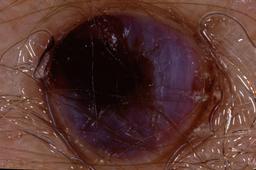

{

"age_approx": 70,

"anatom_site_general": "lower extremity",

"concomitant_biopsy": true,

"dermoscopic_type": "contact non-polarized",

"diagnosis_1": "Benign",

"diagnosis_2": "Benign melanocytic proliferations",

"diagnosis_3": "Nevus",

"diagnosis_4": "Blue nevus",

"diagnosis_5": "Blue nevus, Common",

"diagnosis_confirm_type": "histopathology",

"image_type": "dermoscopic",

"lesion_id": "IL_2232402",

"melanocytic": true,

"patient_id": "IP_0695069",

"sex": "female"

}